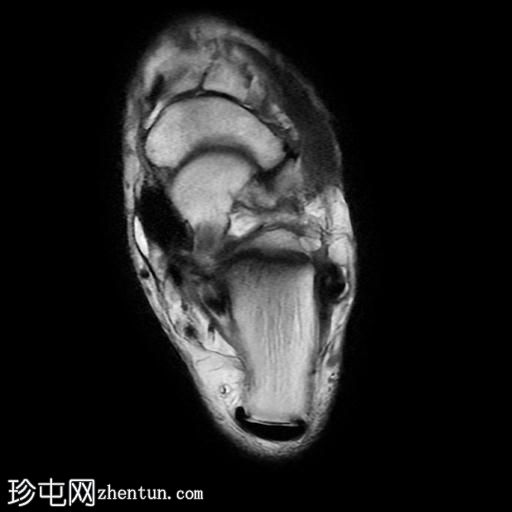

MRI

矢状位

PD脂肪抑制序列

冠状位

T1加权像

冠状位PD脂肪抑制序列

轴位

T2加权像

跟骨前突延长增宽,与舟骨形成不规则关节,形似“食蚁兽

鼻

”。

该异常跟舟关节处可见关节下骨髓水肿。此外,舟骨内外侧径增宽,向外侧逐渐变细,并与增大的跟骨前突形成关节。

距舟关节轻度积液,并可见边缘骨赘。